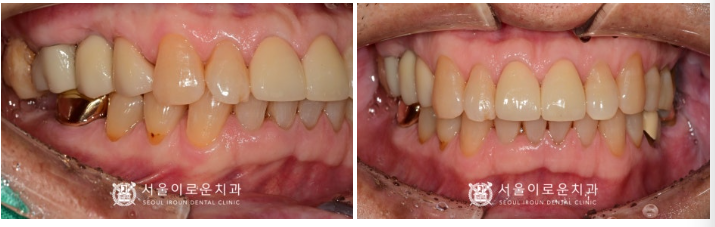

임플란트와 크라운 보철 치료가

마무리 된 사진입니다.

환.자분께서는

통증이 사라지고,

앞니가 자연럽고 예쁘게 되었다며

치료 후 정말 만.족해하셨답니다!

✅ 전 > 후 ✅

(2024.06.07ㅡ>2024.11.23)